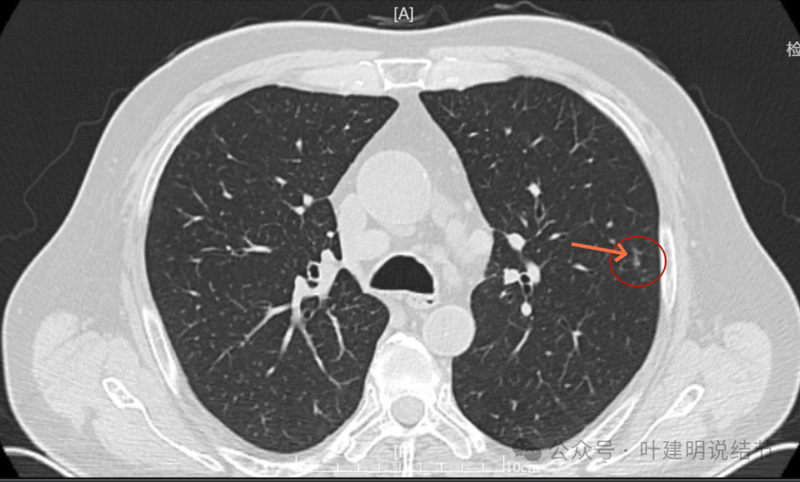

明显实性成分,灶边的细支气管有扩张。

血管与之关系密切,实性密度。

边上有细支气管扩张。

血管进入明显,边缘毛糙不光滑。